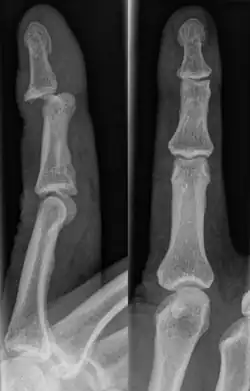

Diagnosis

A jammed finger can generally be diagnosed by a physical examination. Bone or joint deformity may indicate potential dislocations or fractures.[6] The basic structure of the finger includes three bones with joints in between each.[9] The joint closest to the tip is the distal interphalangeal (DIP) joint. The next joint, moving closer to the hand, is the proximal interphalangeal (PIP) joint. The thumb differs by only having two bones and one interphalangeal joint.[10]

The injured finger may be examined to determine where the pain is worst.[3] If the finger is sprained or dislocated, pain will be worse at the joint rather than the bone.[3] Due to the risk of dislocations or fractures, X-rays should be conducted prior to testing joint stability. This allows for prior detection of a dislocation or fracture.[3] It is recommended that a variety of views (lateral, oblique, and anteroposterior) are observed.[3] In extremely painful cases, a digital nerve block may be done to better assess the finger. This is where anesthetic is injected to either side of the base of the affected finger to reduce pain.[3]

Fractures

Fractures are instances where the bone's structural integrity has been compromised.[20] If a jammed finger produces a fracture, pain will be greatest at the bone as opposed to the joint.[2] There may also be visual deformation of the bone itself.[6] As with any skeletal injury, an x-ray can be conducted to verify the presence of a fracture.[1] The distal phalanx is especially vulnerable to avulsion fractures.[1] These avulsion fractures are common following a first time dislocation of the DIP.[1]